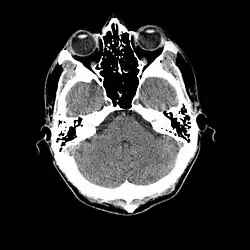

More recently, computed tomography has played a large role in reconstructing endocasts. The procedure is non-invasive and has the advantage of being able to analyze a fossil in record time with little risk of damaging the fossil under review. CT imaging is achieved through the application of x-rays to produce tomographs, or sectional density images, which are similar to the images produced during MRI scans.[8] CT scans use slices approximately 1 mm thick to reconstruct a virtual model of the specimen.[9] This method is especially useful when a fossil cranium is occupied by a natural endocast that cannot be removed without destroying the skeletal portions of the fossil. Because the cranium and its contents are of different densities, the endocranial cavity and its unique traits can be reconstructed virtually.[8]

Radiographic technique such as computed tomographic imaging, or CT scans, coupled with computer programming have been used to analyze brain endocasts from as early as 1906.[10] Recent development of advanced computer graphics technology have allowed scientists to more accurately analyze of brain endocasts. M. Vannier and G. Conroy of Washington University School of Medicine have developed a system that images and analyzes surface morphologies in 3D. Scientists are able to encode surface landmarks that allows them to analyze sulcal length, cortical asymmetries and volume.[11] Radiologist, paleoanthropologists, computer scientists in both the United States and Europe have collaborated to study such fossils using virtual techniques.[10]

Many paleoneurobiologists measure cranial capacity via the submersion method, in which displacement of water in a beaker is taken as the volume of the endocast. Scientists who believe that this method is not accurate enough will use a similar procedure in which a beaker with a spout is filled until it is full. The water displaced by the endocast is then weighed to determine the endocast volume. Although both of these techniques are significantly more precise than previous methods, scientists are optimistic that more advanced techniques such as computed tomography will provide greater accuracy of volume measurements.[7]